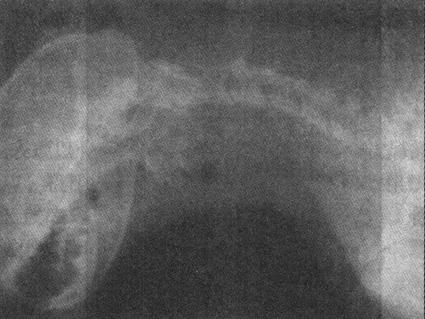

2)脱位 对半脱位和深在性脱位,临床诊断较为困难,须进行X线检查。全脱位的X线表现为关节内两骨端的关节面对应关系完全脱离(图1-2)。半脱位的X线表现是相对应的关节面部分脱离,失去正常相互平行的弧度和间隙。先天性脱位多见于膝关节,X线显示股内踝关节面平坦,外滑车发育不良等。

图1-2 猫左膝关节脱位合并右胫骨近端骨折

侧位显示左膝关节正常位置发生改变,左胫骨向前移位。右胫骨近端骨折、移位重迭,骨干有骨裂